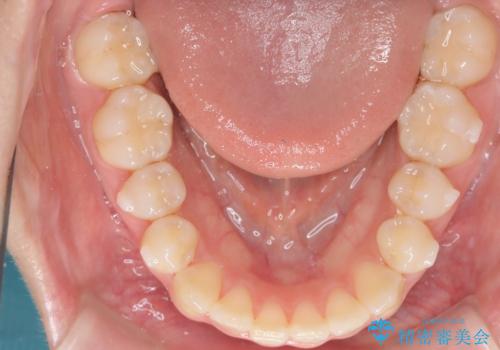

- 右上の前歯(2番)が下の歯より内側に入っている反対咬合を主訴にご来院されました。精密な検査の結果、この反対咬合を解消するためには、右上の歯列に前歯を出すためのスペースを確保する必要があると判明しました。患者様のご希望に合わせ、透明で目立たないインビザライン(マウスピース矯正)による治療計画を立案。奥歯全体を奥へ動かす遠心移動でスペースを作り、反対咬合を解消することを目指します。

今回の矯正治療では、透明なマウスピース型の装置インビザラインを使用しました。治療は、緻密なデジタル計画に基づき、奥歯から順に歯列全体を後方へ移動させる遠心移動を実施し、前歯を前に出すためのスペースを確保しました。このスペースを利用して、内側に入り込んでいた右上2番をスムーズに前方に誘導し、正常な咬み合わせへと改善。目立たないインビザラインで、機能的な咬み合わせと美しい前歯の並びを獲得していただけました。